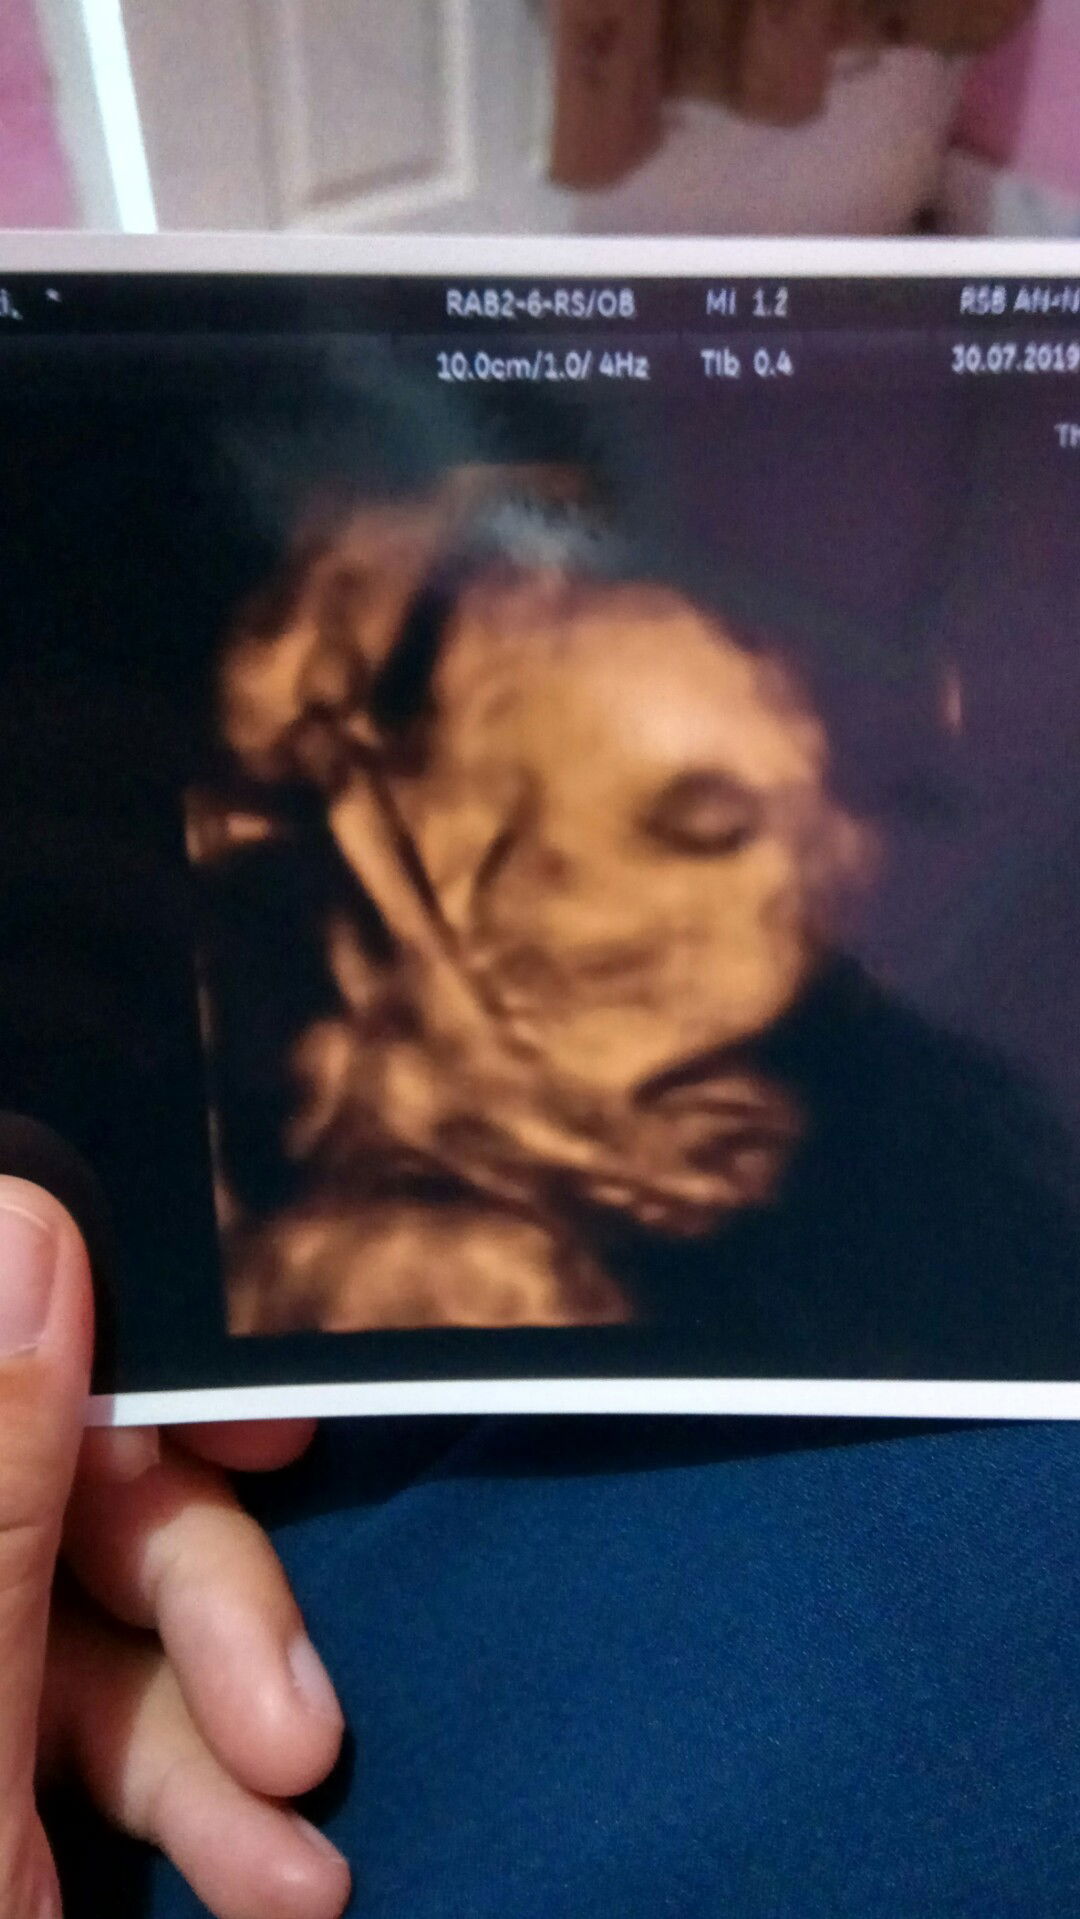

Hasil USG 24 minggu

Bismillaah. Assalamu'alaikum warahmatullahi wabarakatuh bunda. Kemaren saya coba usg 4 dimensi di usia kandungan 24 minggu, tapi kenapa saat di USG wajah bayi terlihat seperti tengkorak ya? Soalnya saya lihat hidung dan mulutnya tidak terlihat jelas. Saya jadi cemas bun ?Waktu saya tanya ke dokternya "Dok, itu kok nggak ada hidungnya ya?", beliau cuma jawab "Ada kok". Kalau boleh share hasil USG bunda saat usia 6 bulan dong bun. Do'akan dedek dalam kandungan saya dan bunda sekalian sehat2 ya bun. Terimakasih ???